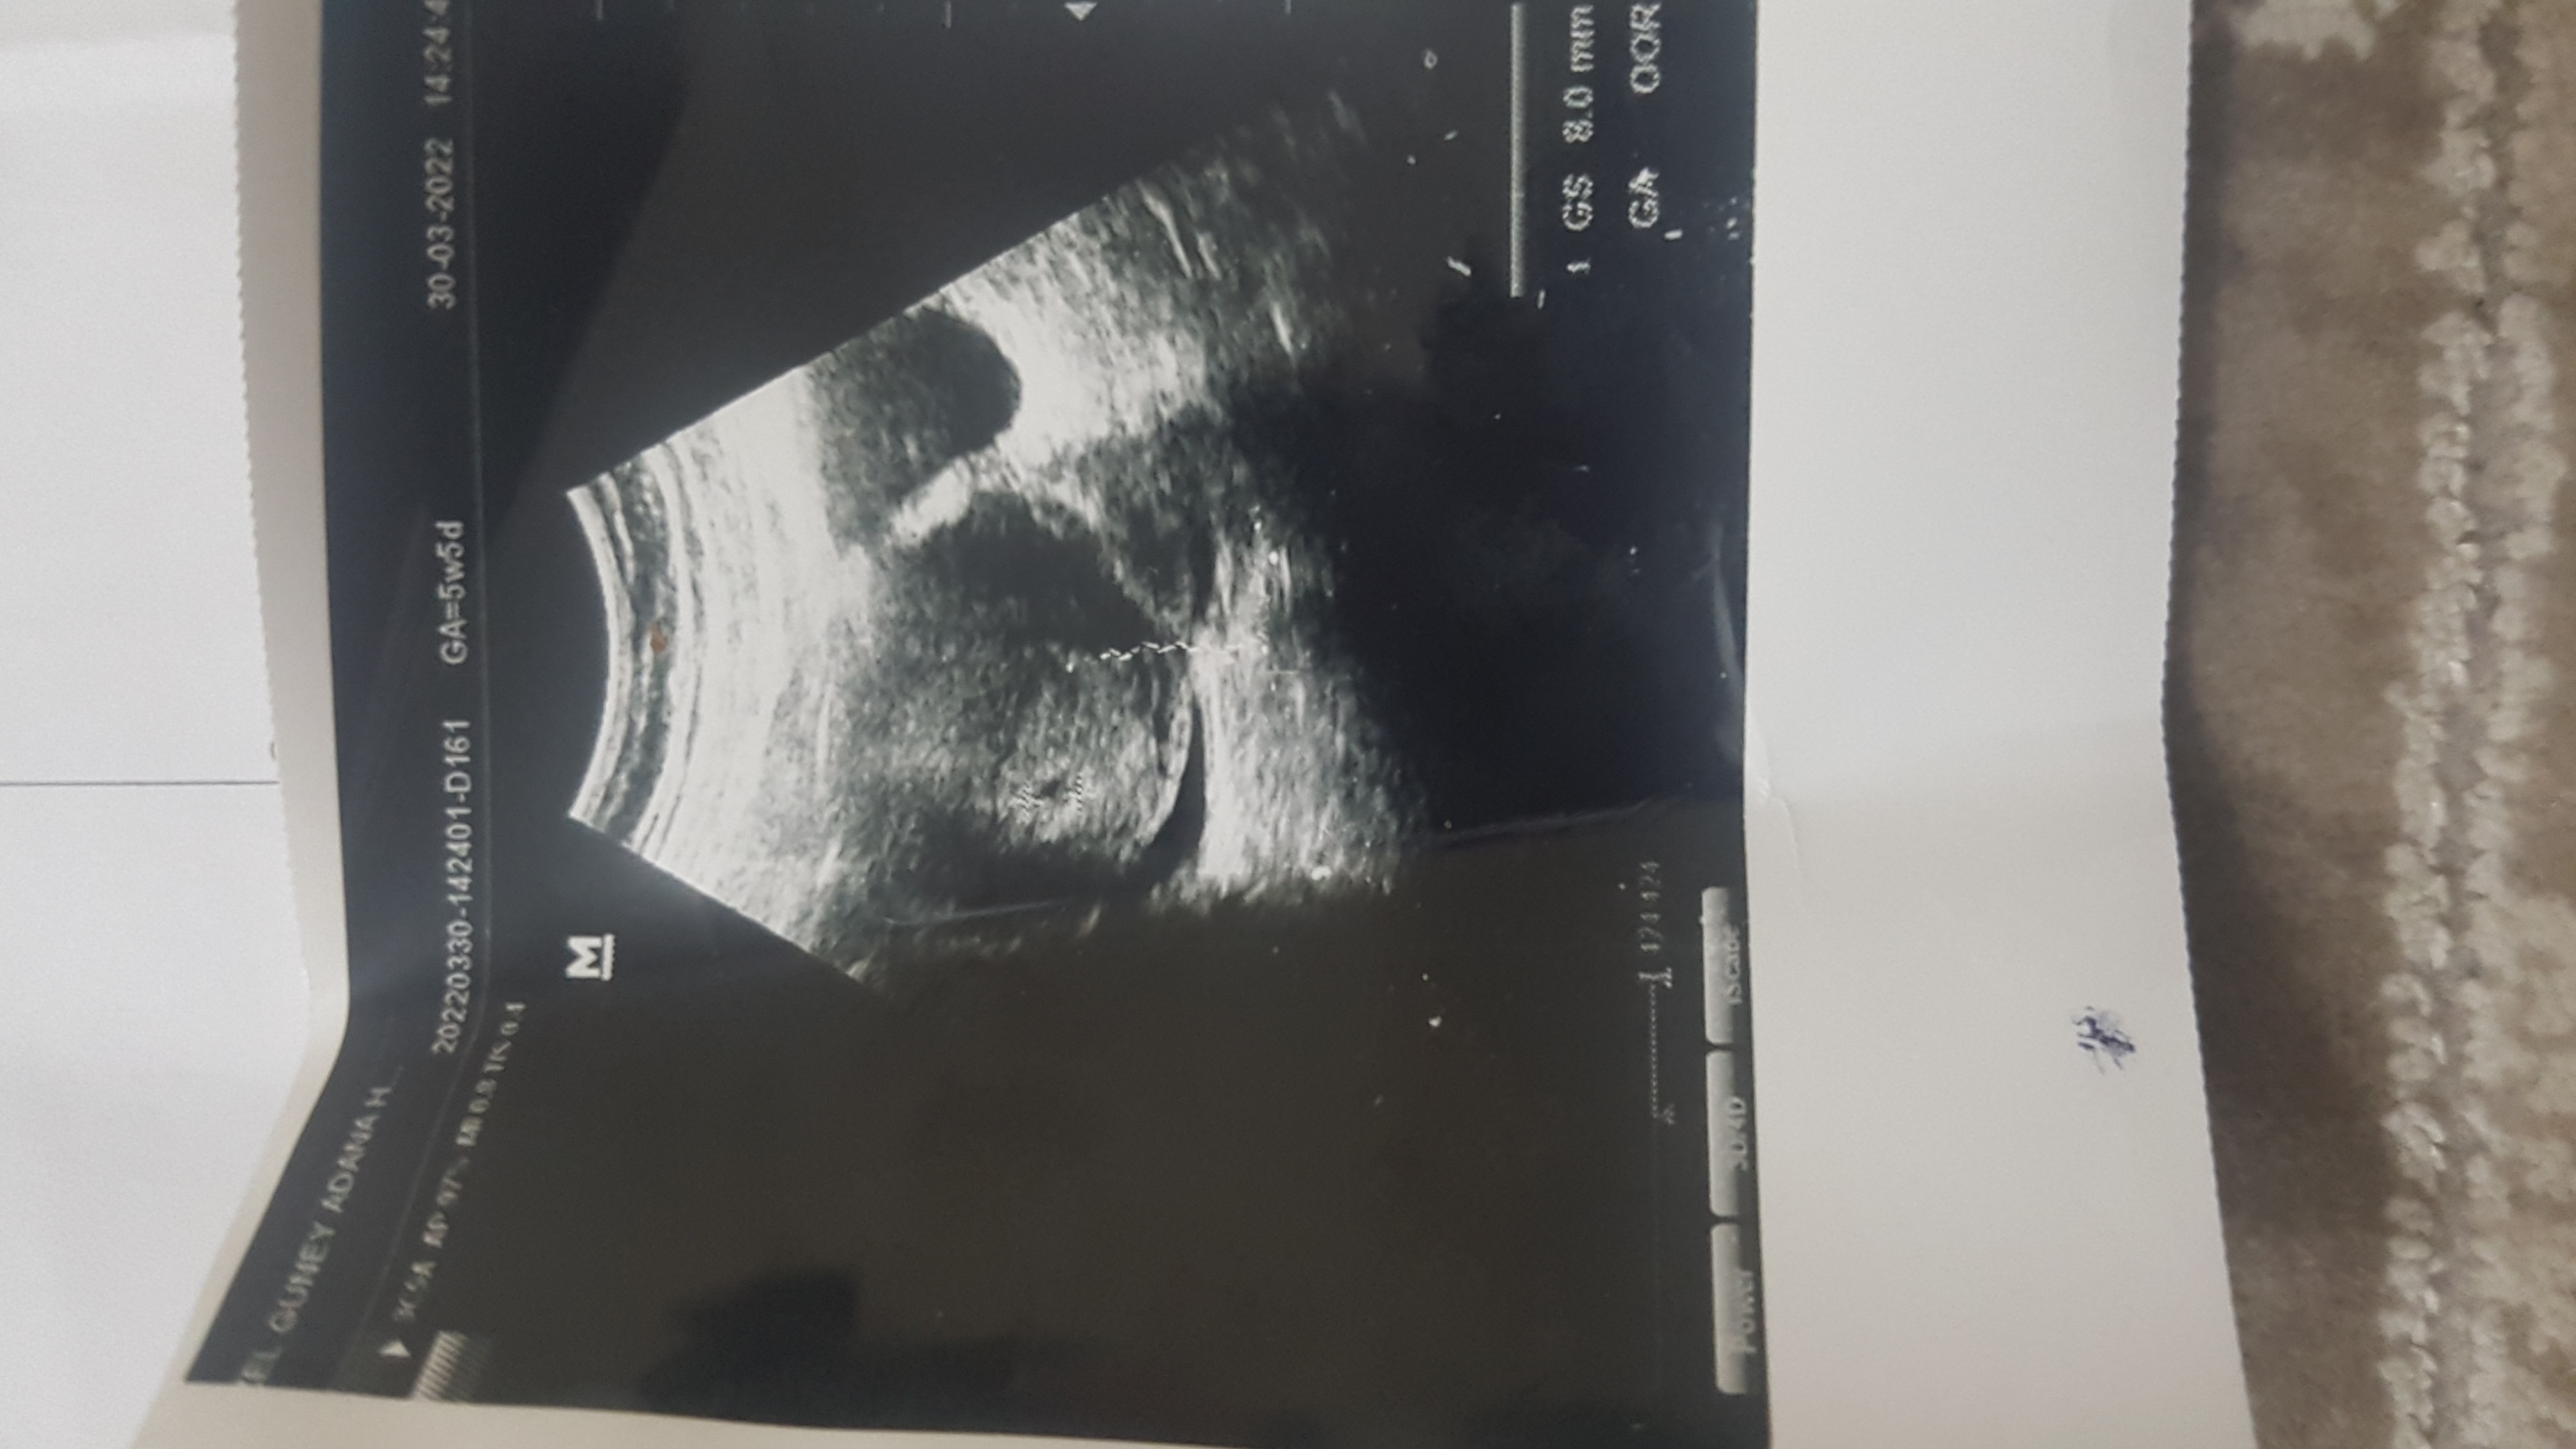

20220330_195946.jpg

Kızlar selam ben yeni üye oldum 5 haftalık gebeyım sizce cinsiyeti ne 😊 2. Gebligim